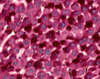

Parietal (A) & Chief Cells (B) in Stomach

Fundic gland - lumina (L) of the fundic glands can be recognized. The chief cells (CC) are granular in appearance and are much smaller than the round, plate like parietal cells (PC). Parietal cells, so their name imply, are located at the periphery of the gland. Slender connective tissue elements (CT), housing blood vessels, occupy the narrow space between the closely packed glands.